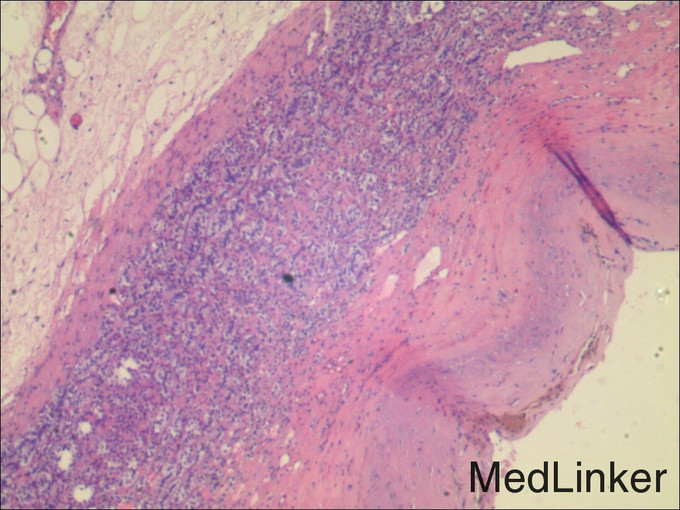

术后病理检查结论/诊断:(左肾上腺囊肿)送检8X7X3cm碎组织一堆,囊壁样,带脂肪,囊壁光滑。镜下:送检肾上腺组织内可见由纤维组织组成的囊壁样结构,其内表面未见被覆上皮,病变符合肾上腺囊肿。 肾上腺肿物有哪些常见类型?